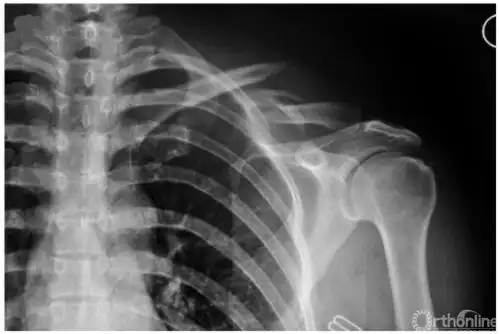

肩关节正位

x线从患者背后穿透,患者前胸紧贴探测平板,双手背于髂骨上,肩部下垂